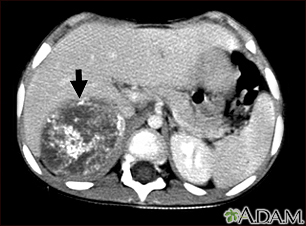

Neuroblastoma in the liver - CT scanBackNeuroblastoma in the liver - CT scanThis CT scan of the upper abdomen shows a large tumor (neuroblastoma) on the person's right side (lower left side of picture). The tumor is behind the liver and is pushing the liver forward and may have possibly spread into the liver tissue. E-mail FormEmail ResultsName:Email address:Recipients Name:Recipients address:Message: